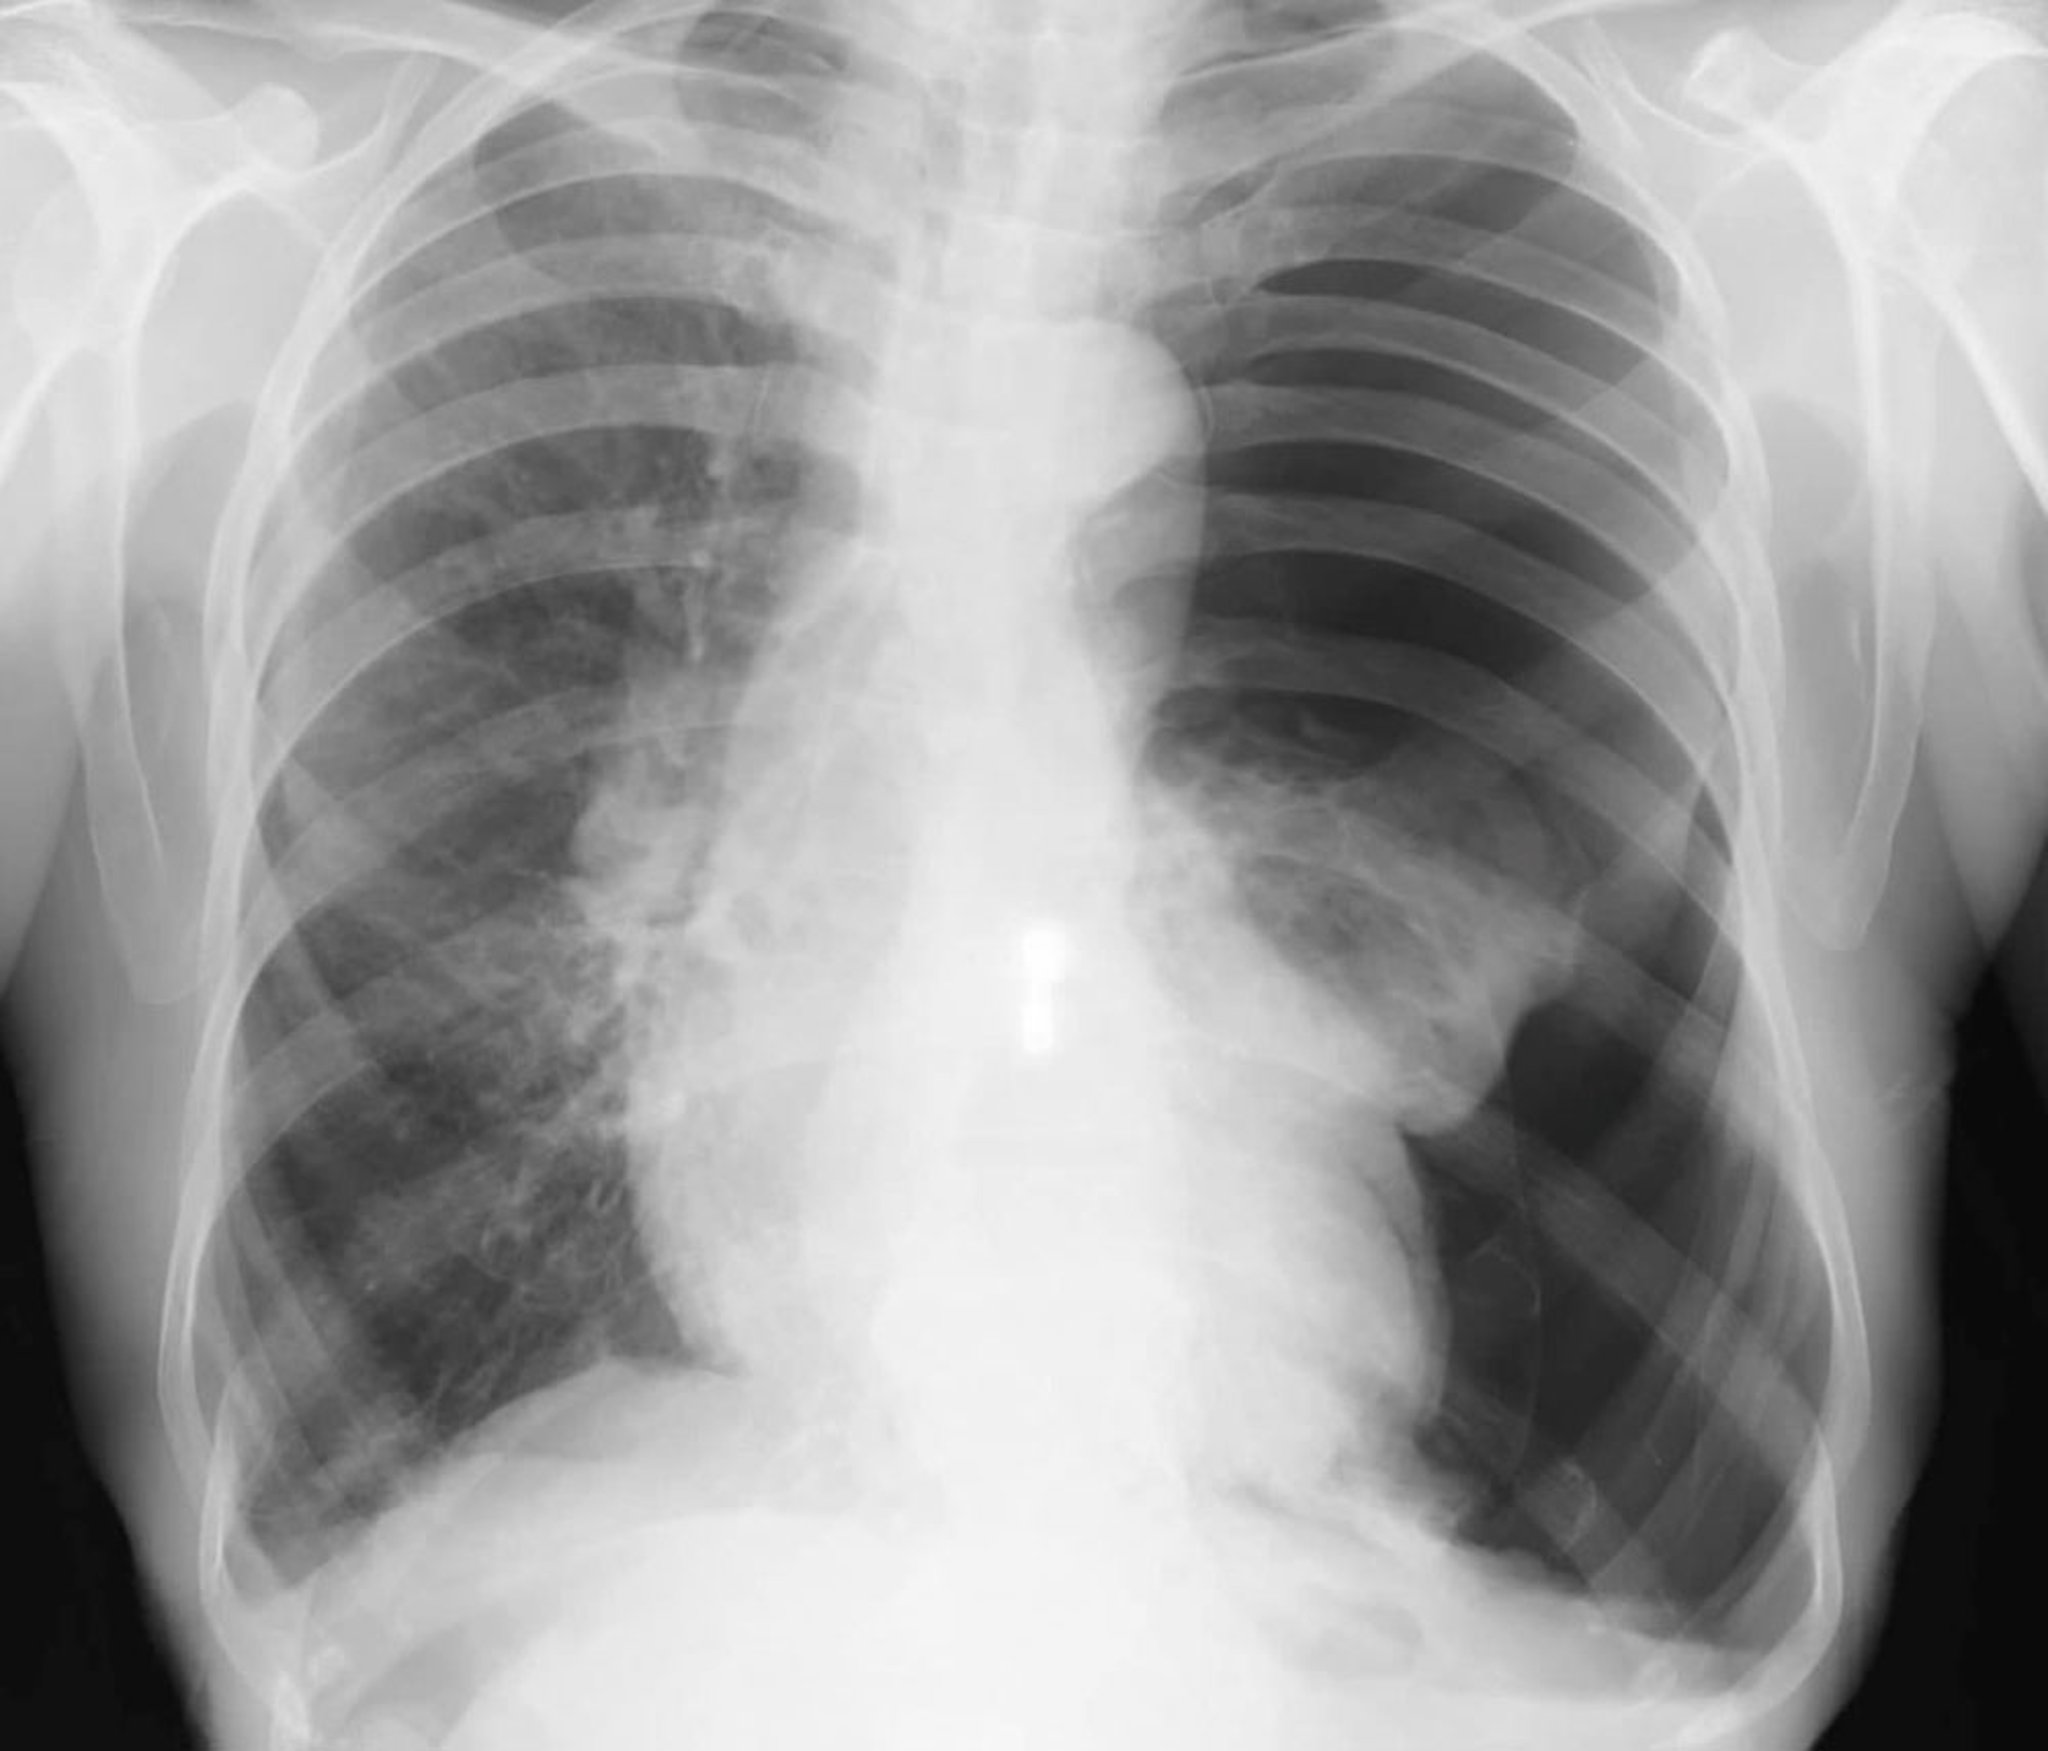

对于病情稳定但有呼吸困难或胸膜炎性胸痛的患者应怀疑该诊断,通常通过直立吸气性胸部 X 线检查确诊。若拍摄呼气相X光片,肺组织密度会增高,从而增强胸膜腔空气与邻近肺组织(因呼气状态和肺不张导致含气量减少)之间的对比差异。萎陷的肺和壁层胸膜之间存在无肺纹理的透亮气体区可诊断气胸。气管偏移和纵隔移位见于大范围气胸。如果潜在的肺部疾病不妨碍充分成像,也可使用床边超声进行诊断。

少量气胸(如<10%)有时在胸片上会被忽视。对可能存在气胸的患者,应在胸片上追溯肺纹理直至胸膜边缘。即使是大量气胸在仰卧位X光片上也可能不明显,应特别注意深沟征(肋膈角异常加深),这可能是仰卧位患者X光片上气胸的唯一征象。影像学上类似气胸的情况包括肺气肿性肺大疱、皮肤皱褶,床单褶皱以及肺野上的胃肠重叠影。